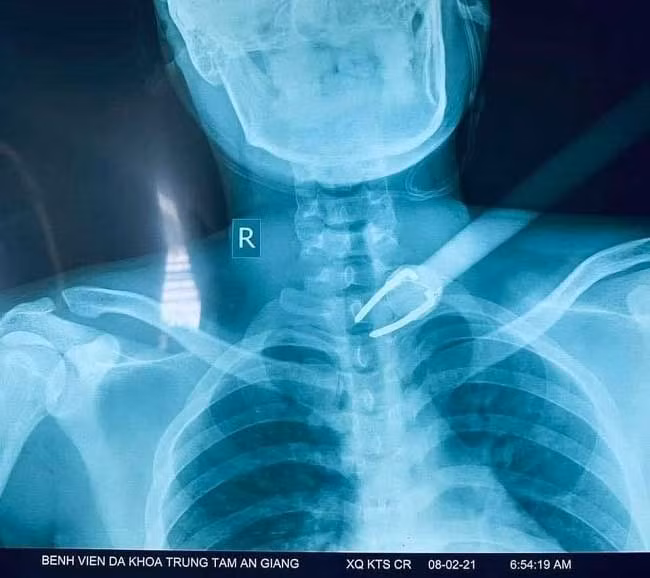

Sáng sớm ngày 8/2, nạn nhân P.Q.D. nam sinh 19 tuổi (ngụ Long Điền B, Chợ Mới, An Giang) phát hiện 2 kẻ trộm chó tại nhà riêng nên cùng cha ruột chạy xe đuổi theo bắt trộm. Tuy nhiên, kẻ trộm hung hãn dùng nỏ tự chế bắn một mũi tên vào ngay vùng cổ nạn nhân đang chạy phía sau.

Mũi tên được lấy ra an toàn dài 50cm với phần mũi kim loại chia làm 2 ngàm dài 8cm với mũi chĩa chỉ 2mm đường kính.

Sau phẫu thuật, các bác sĩ ghi nhận: mũi tên đâm xuyên vào vùng cơ đến tận đốt sống cổ C7-D1.

Tuy vậy, rất may mắn là mũi tên chỉ gây bóc tách cơ vùng cổ - ngực mà không gây thủng hay tổn thương “mạch máu - thần kinh - khí quản - thực quản”. Điều này đóng vai trò vô cùng quan trọng trong việc giữ lại mạng sống cũng như chức năng sống cơ bản cho bệnh nhân.